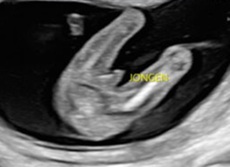

Vanaf 15 weken kun je bij ons terecht voor een geslachtsecho. Bij deze echo, die ongeveer 15 min duurt, kunnen we zien of je een jongen of een meisje verwacht. Wil je het geslacht meteen horen, of het juist in een gesloten envelop voor een gender reveal? Alles is mogelijk en natuurlijk krijg je ook een foto mee.

Soms ligt je baby niet op de ideale manier om het geslacht duidelijk te zien. In dat geval doen we ons best om het alsnog te bepalen. Als het niet lukt, plannen we een nieuwe echo in, zodat je alsnog het geslacht van jouw baby te weten komt. We doen ons uiterste best om het geslacht correct te bepalen, maar het is belangrijk om te weten dat het nooit 100% zeker is.